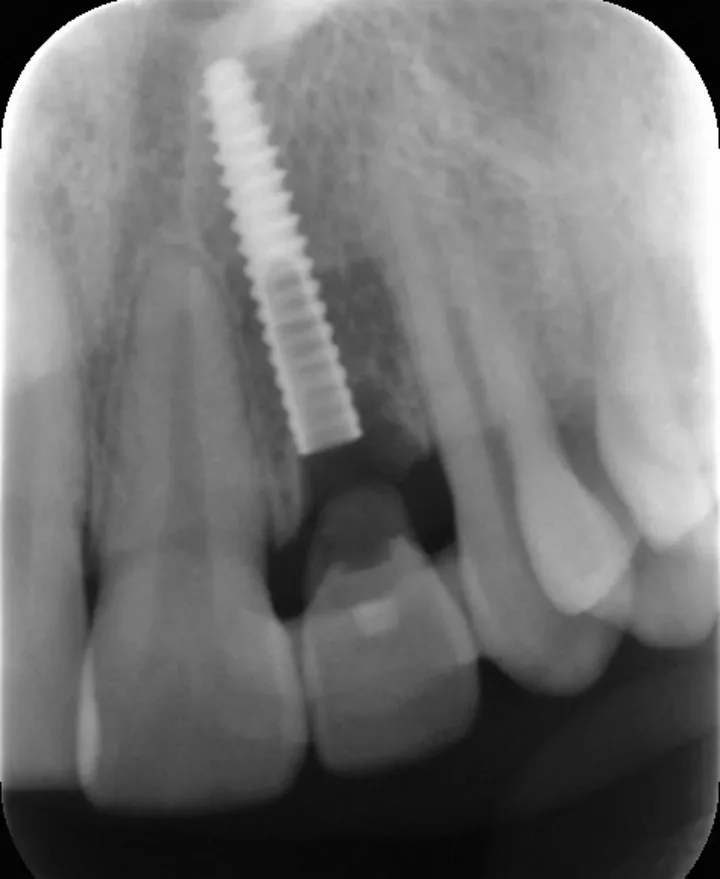

图 24 :植入 Axiom® 2.8 x 14 种植体。

图 26 :术后 X 线检查。